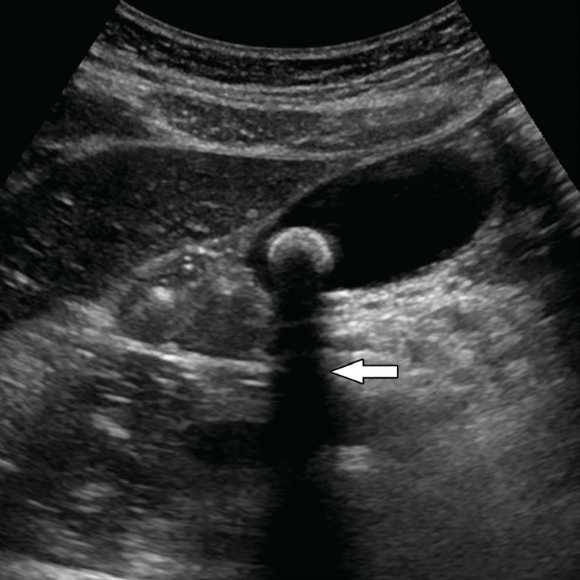

Name this artifact.

What is the cause of the artifact?

Reverberation: Occurs at highly reflective surfaces (e.g., tissue-gas interface). Some echoes are reflected back and forth between gas and transducer, then interpreted to exist at twice the depth of the original interface.